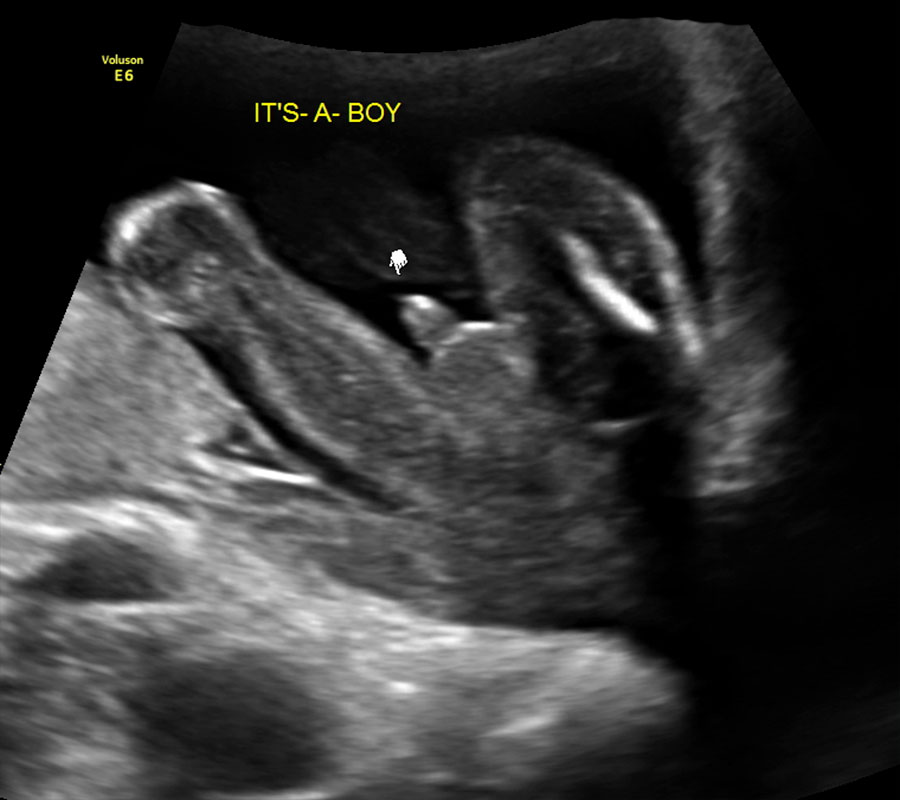

what does a boy look like on ultrasound

Early Gender Boys 15 Weeks | 3D 4D 5D HD Ultrasound Michigan

Early Gender Boys 15 Weeks | 3D 4D 5D HD Ultrasound Michigan

Early Gender Boys 15 Weeks | 3D 4D 5D HD Ultrasound Michigan

Early Gender Boys 14 Weeks | 3D 4D 5D HD Ultrasound Michigan

Early Gender Boys 15 Weeks | 3D 4D 5D HD Ultrasound Michigan

A 20 Week Male Gender Guess | Ultrasound Unwrapped

Dad Diary: 15 Weeks 3 days 4D Ultrasound BOY

Do you think this is 100% a boy at 15 weeks ? I am googling mis …